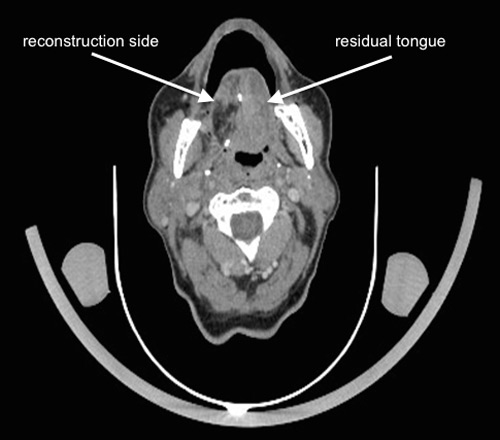

Figure 2

Follow-up contrast enhanced computed tomography part from a 18F-FDG-PET/CT scan 6 months following right partial glossectomy, elective neck dissection and reconstruction of the tongue with a radial forearm free flap for a pT2 pN1 squamous cell carcinoma. The primary site cannot be evaluated exactly regarding local recurrence. There are no evident suspicious lymph nodes to be detected.